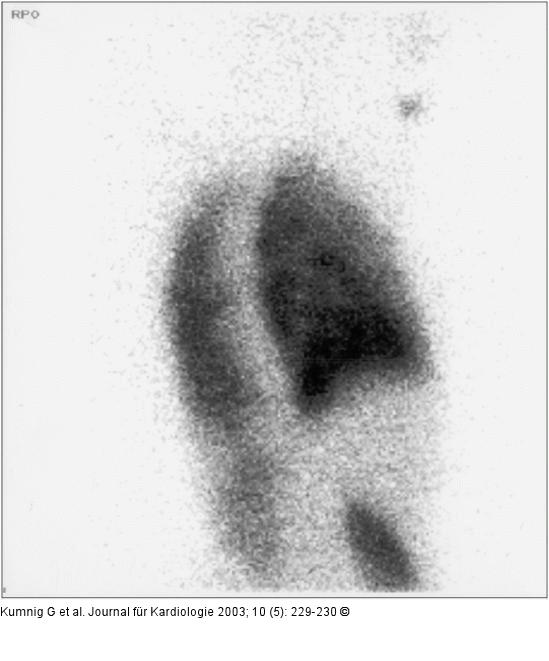

Abbildung 2: Lungenperfusionsszintigraphie Lungenperfusionsszintigramm von rechts-posterior-oblique. In den Schrägprojetionen deutliche Darstellung der rechten Niere. Die Schilddrüse und die Speicheldrüsen kommen als Hinweis auf freies Pertechnetat nicht zur Darstellung |

Lungenperfusionsszintigramm von rechts-posterior-oblique. In den Schrägprojetionen deutliche Darstellung der rechten Niere. Die Schilddrüse und die Speicheldrüsen kommen als Hinweis auf freies Pertechnetat nicht zur Darstellung |